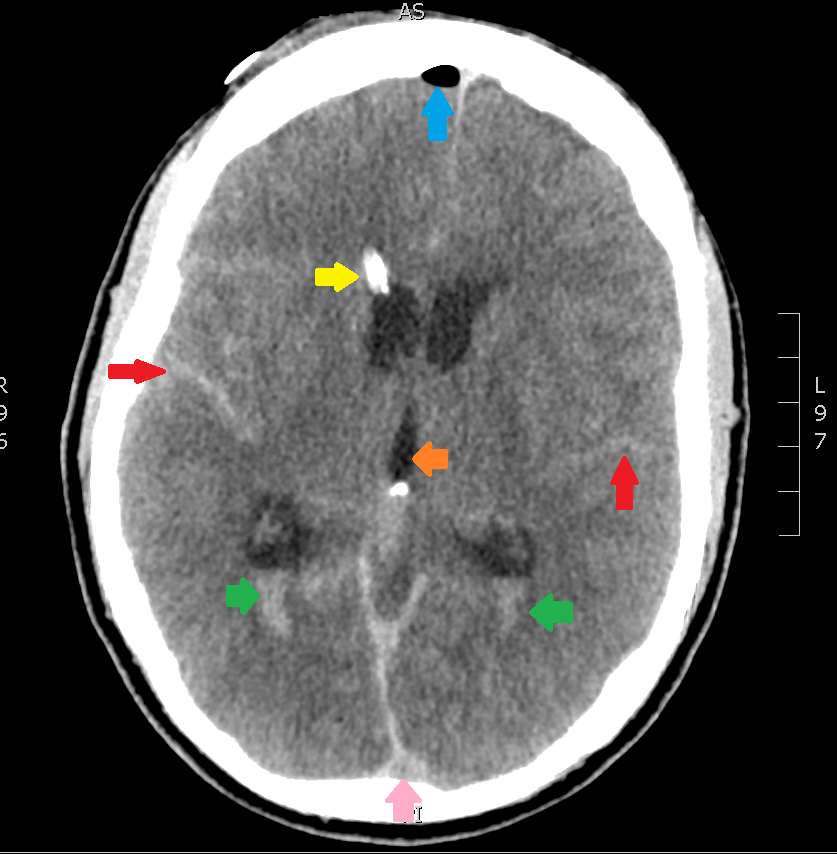

Now, let’s get into the specifics of the axial image. Scroll down for the key.

The highlighted structures are:

- Red Arrow – subarachnoid blood; you know it’s blood because it’s hyperdense, and it’s subarachnoid because it’s settled inside the cerebral gyri.

- Green Arrows – this is intraventricular blood, layering out in the bottoms of the lateral ventricles due to gravity (in this case, the source is the subarachnoid blood).

- Yellow Arrow – a tricky one, this is a ventricular drain, or EVD – commonly used to prevent the development of hydrocephalus after subarachnoid hemorrhage. Look for it again in the coronal and sagittal images above.

- Blue Arrow – Free air, given how hypodense it is, and it has found its way to the top of the cranium, as you would expect an air bubble to do. The source if the EVD.

- Orange Arrow – The third ventricle

- Pink Arrow – Dural venous sinus

If you go back to the coronal and sagittal images you can try to find the same structures. You’ll also see that there is a fair amount of subarachnoid hemorrhage anterior to the brain stem.